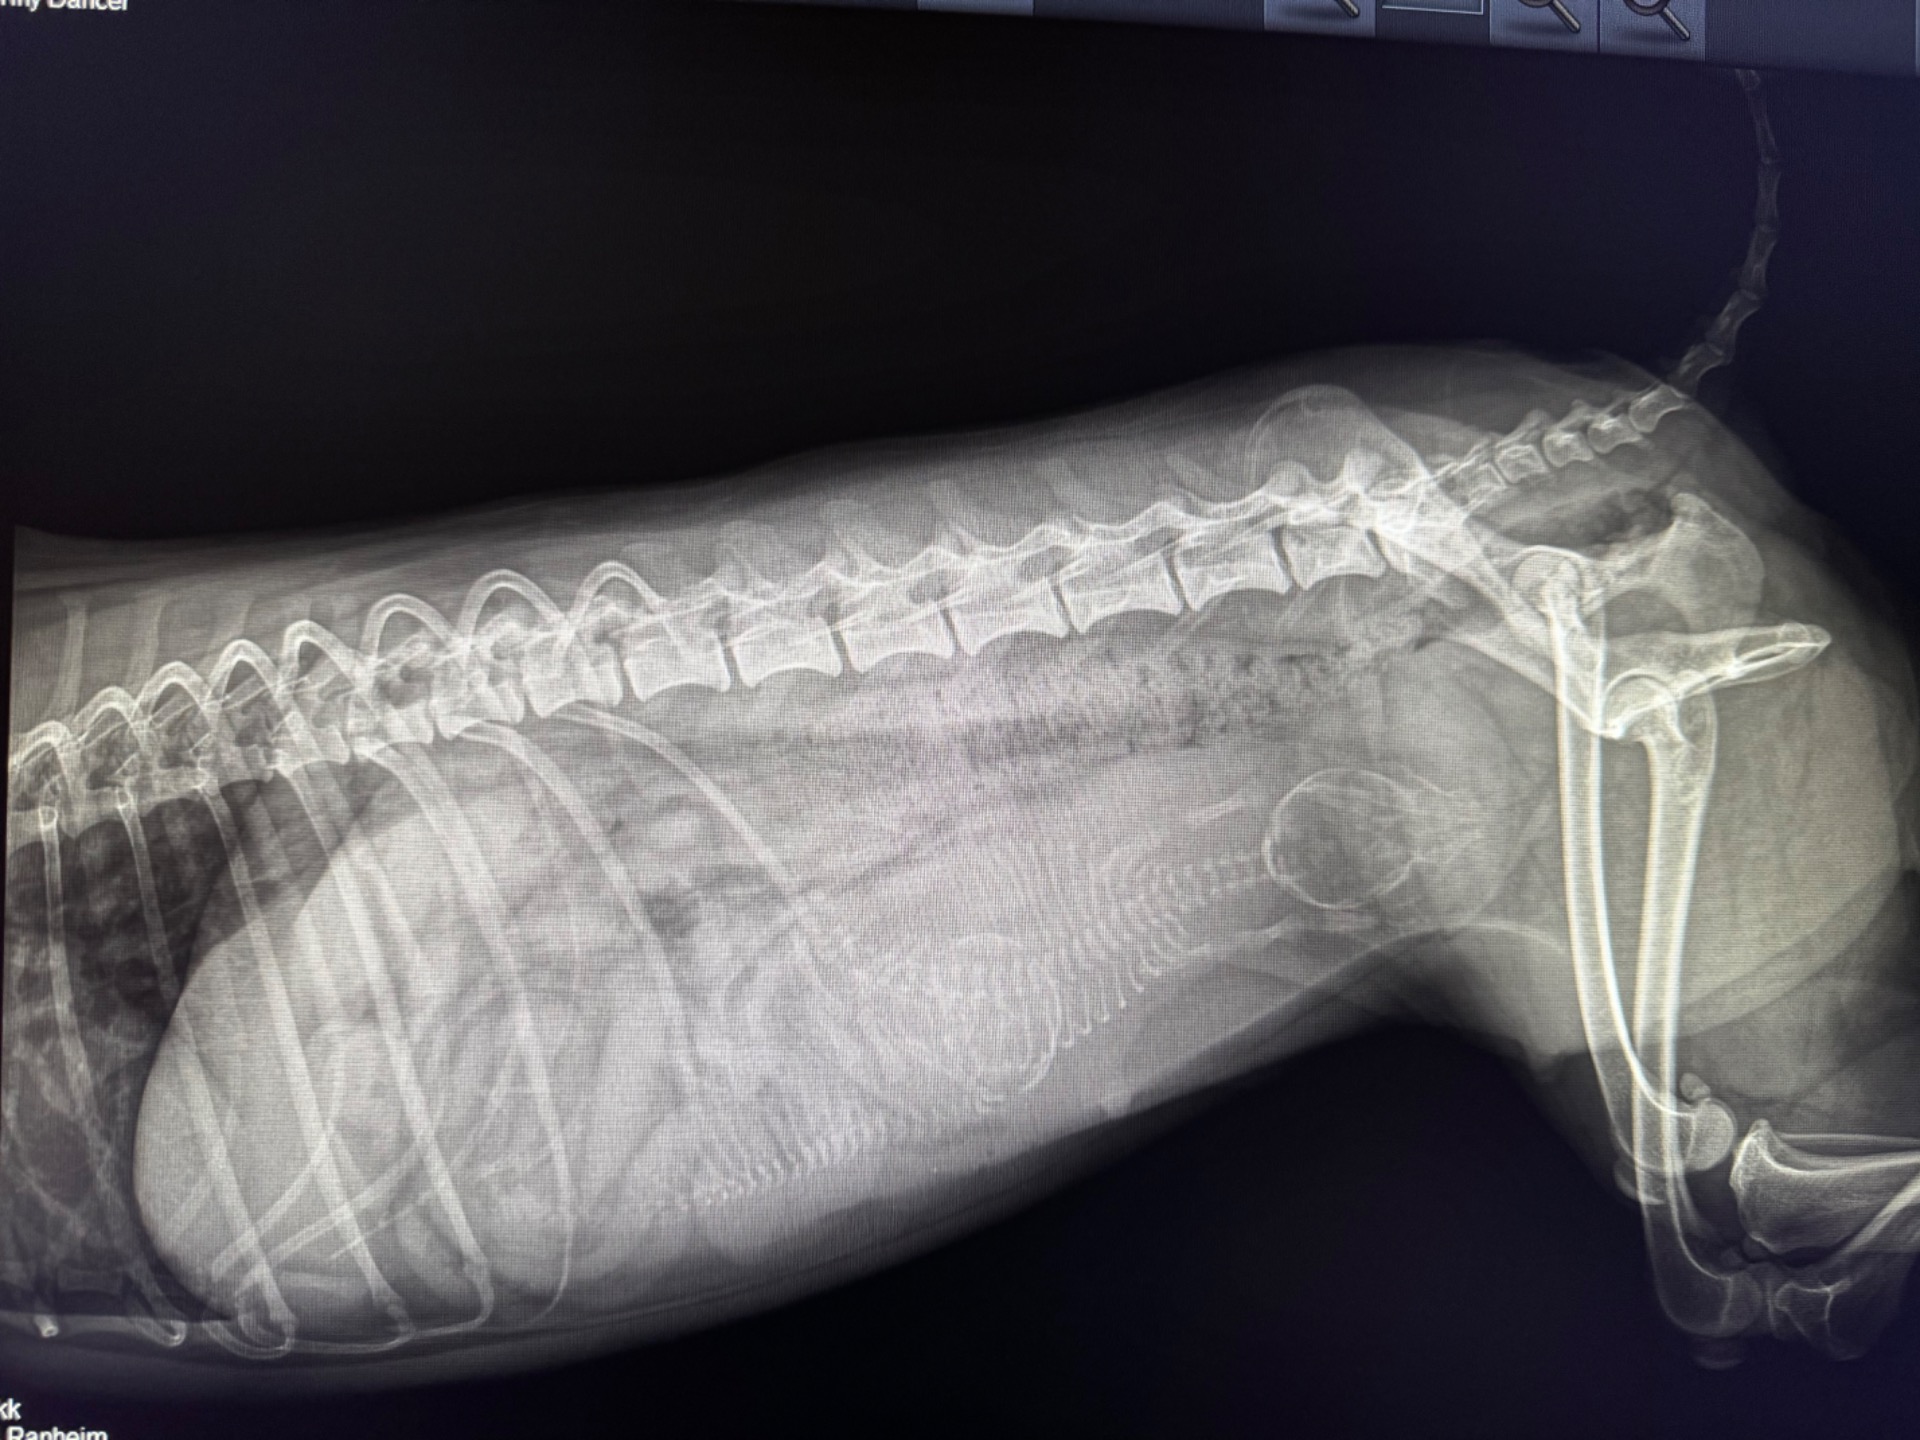

Røntgen

Røntgen bilde ble tatt 06.02.2026. Her ser man at det er 2 søte små valper inne i magen til Villemo, dette er på Dag 54 i graviditeten. De vises veldig godt :-)